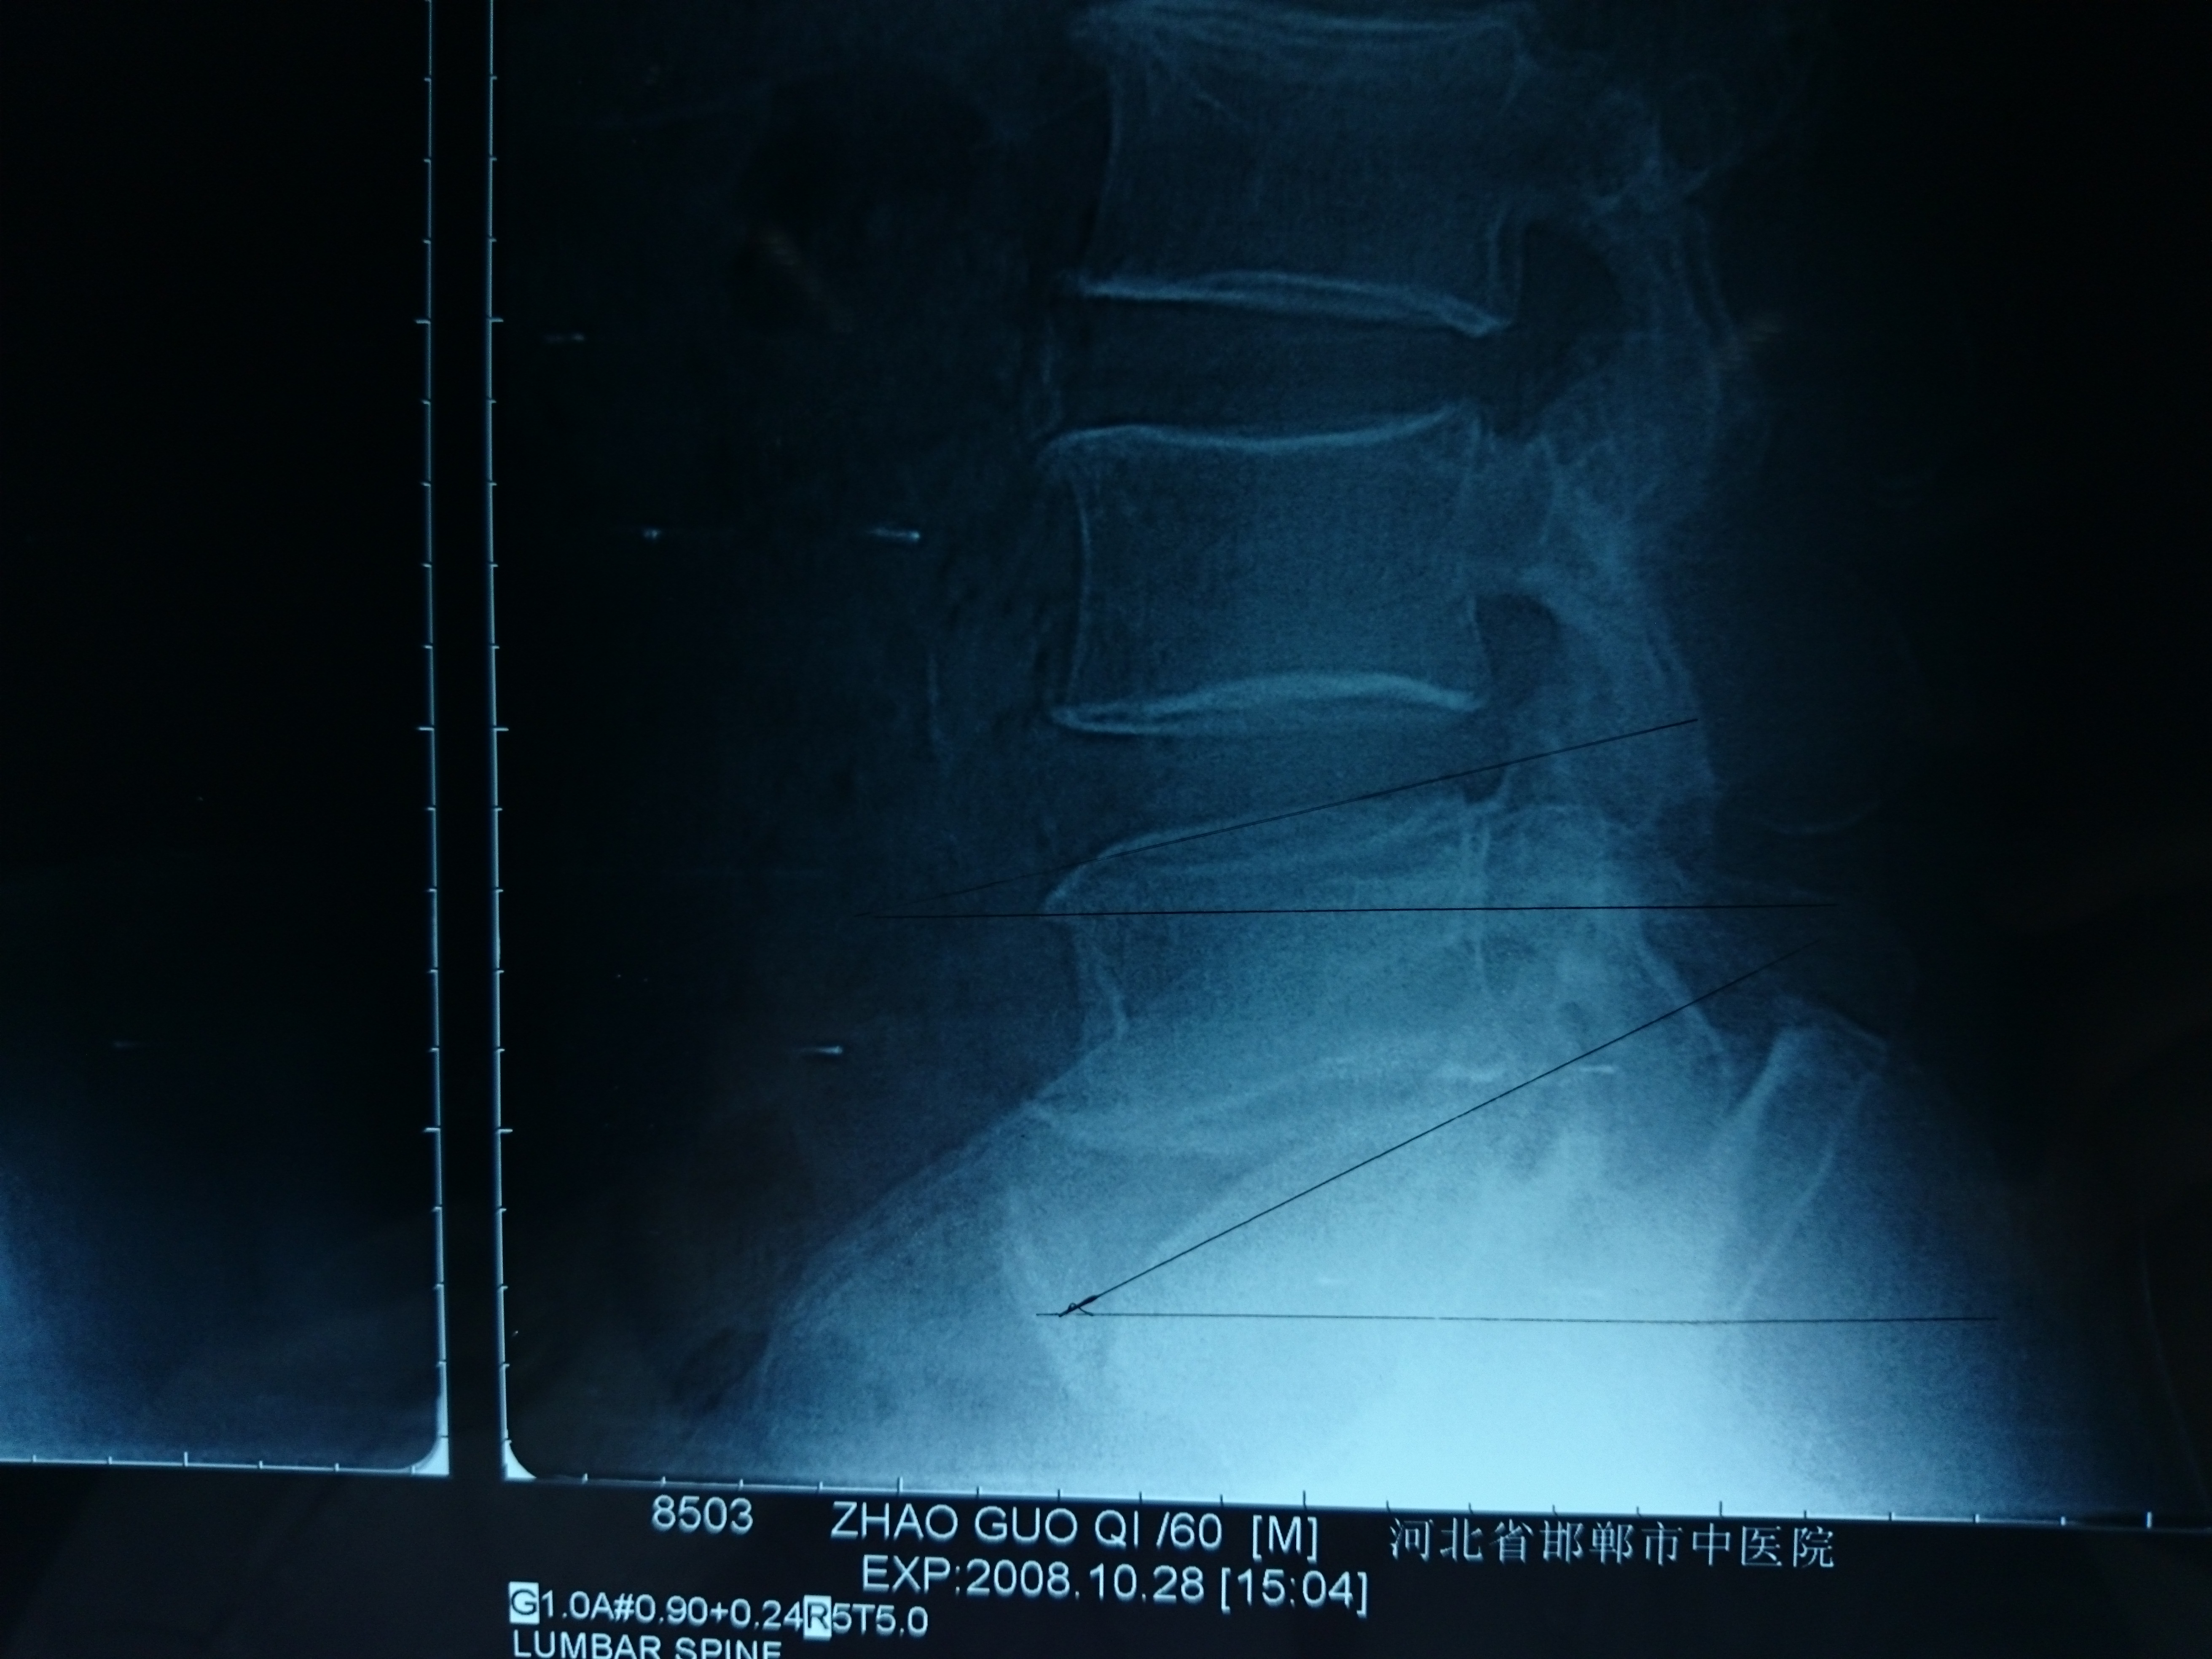

首页 > 张恒云工作室 > 影像资料 三十四